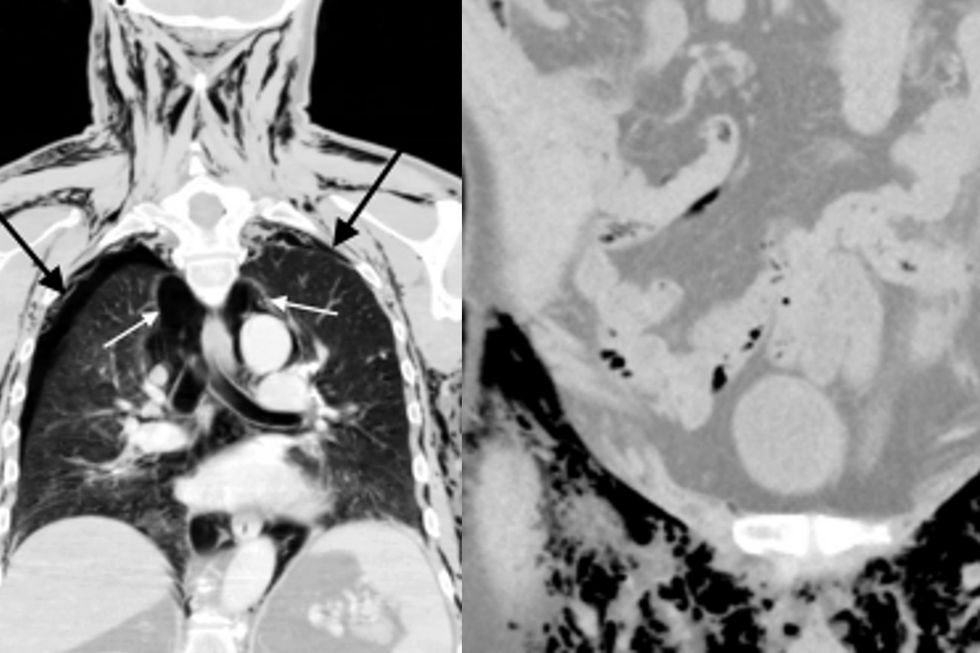

In addition, his X-ray results revealed there was excessive air trapped in his chest, which could have been fatal if untreated.

Medical professionals inserted two plastic tubes into his chest to get rid of the excess air before the man was transferred to another hospital for further treatment.